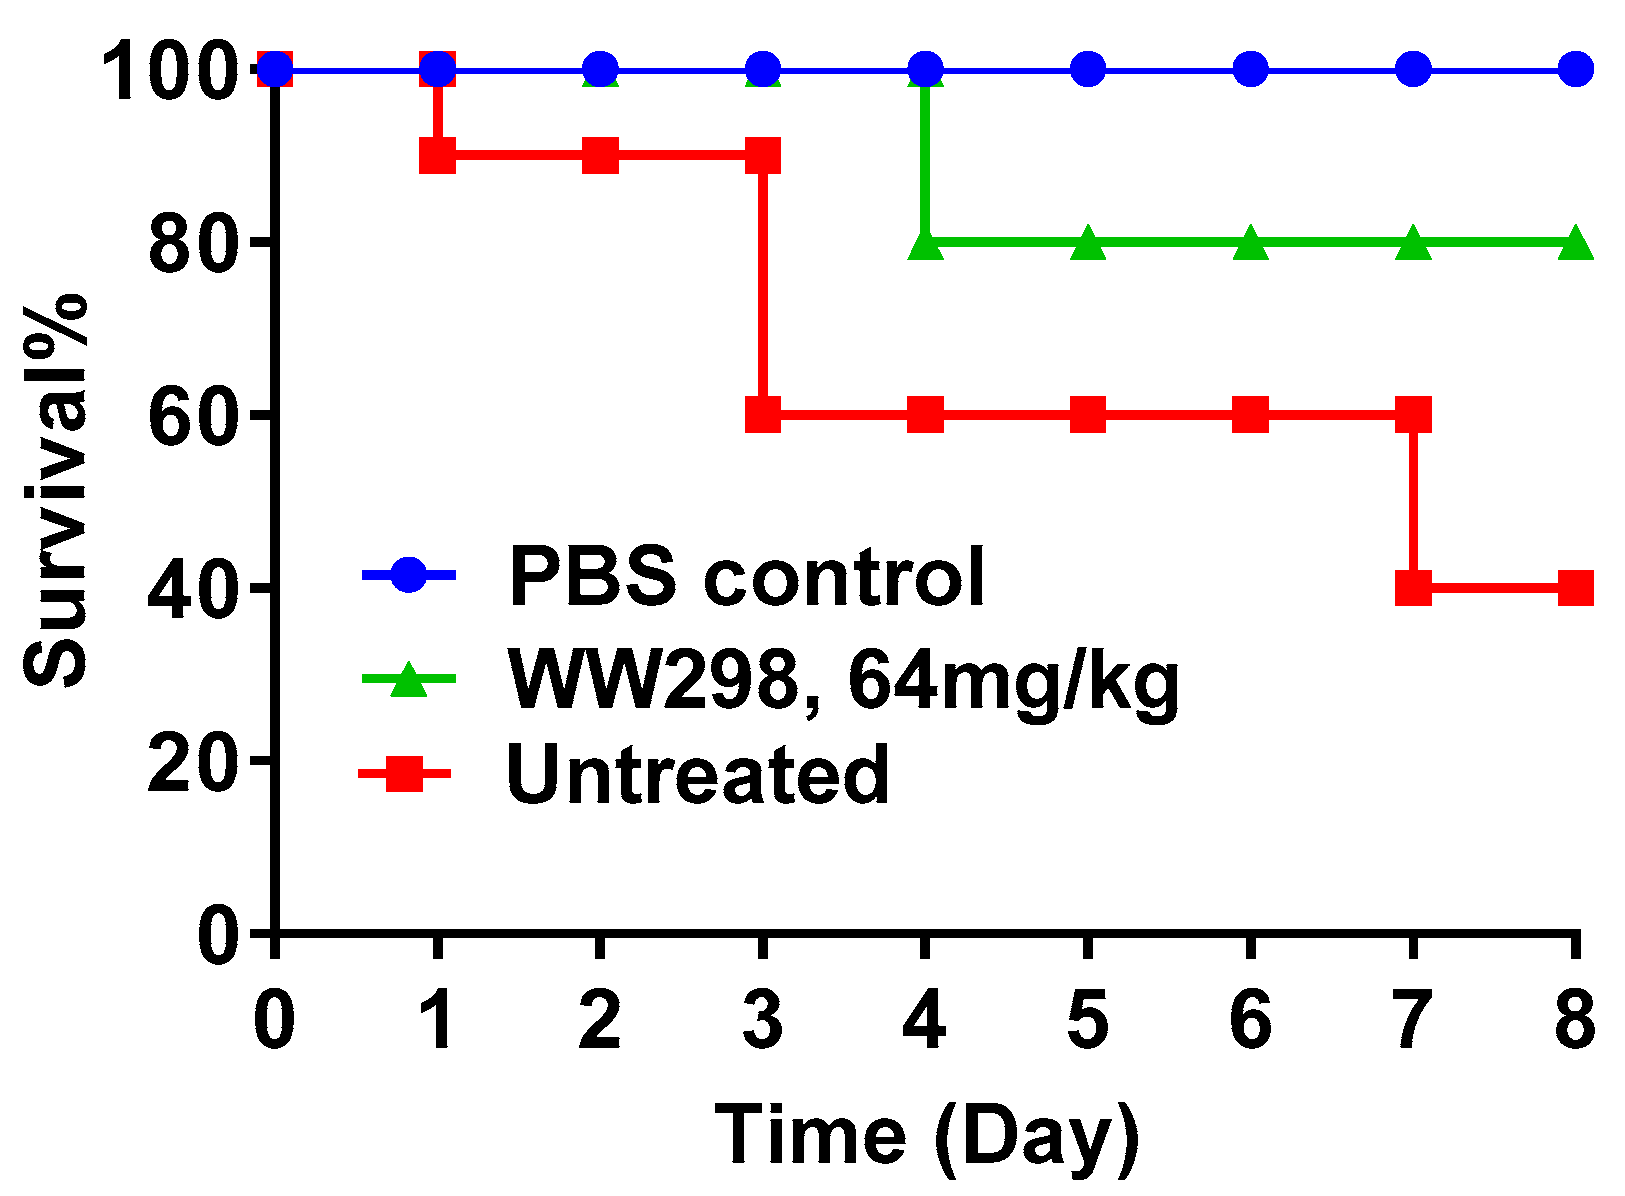

2.8. Protection of Galleria Mellonella Wax Moths from MRSA Infection

4.13. Protection of Invertebrates from Death